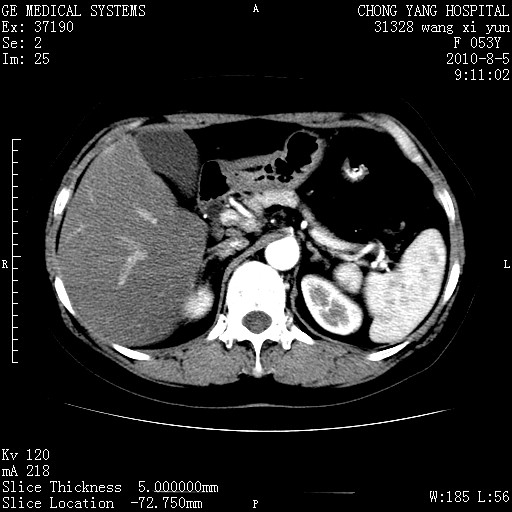

标题: CT28214:F41Y 血尿二十天,建议盆腔平扫加增强。

胆管细胞ca?

1)考虑肝左叶胆管细胞癌。2)脂肪肝。

支持胆管细胞ca。